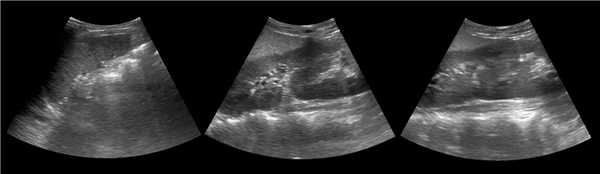

В положении пациента на спине по среднеключичной и переднеподмышечной линии выводим правую почку в соседстве с печенью, а левую почку вблизи селезенки. Оцените эхогенность почек. Корковый слой почки в норме изо- или гипоэхогенный по отношению к печени и гипоэхогенный по отношению к селезенке.

Рисунок. Эхогенность органов сравнивают на одном срезе. На УЗИ нормальная почка по соседству с печенью (1) и селезенкой (2). У детей до 6 месяцев паренхима почек в норме может быть гиперэхогенной по сравнению с печенью (3).

Эхоструктура почек

В нормальной почке пирамиды гипоэхогенные, корковое вещество и колонны Бертини изоэхогенны друг другу. В синусе располагается в норме невидимый ЧЛК, гиперэхогенная соединительная и жировая ткань, гипоэхогенные сосуды и вершины пирамид.

Когда различают пирамиды, корковое вещество, почечные колонны, то эхоструктура паренхимы почки не изменена. Если их не видно, то эхоструктура изменена за счет отсутствия четкой корково-мозговой дифференциации.

Рисунок. На УЗИ почка с неизмененной эхоструктурой: гипоэхогенный по отношению печени корковый слой и колонны Бертини, почти анэхогенные пирамиды, гиперэхогенный синус.